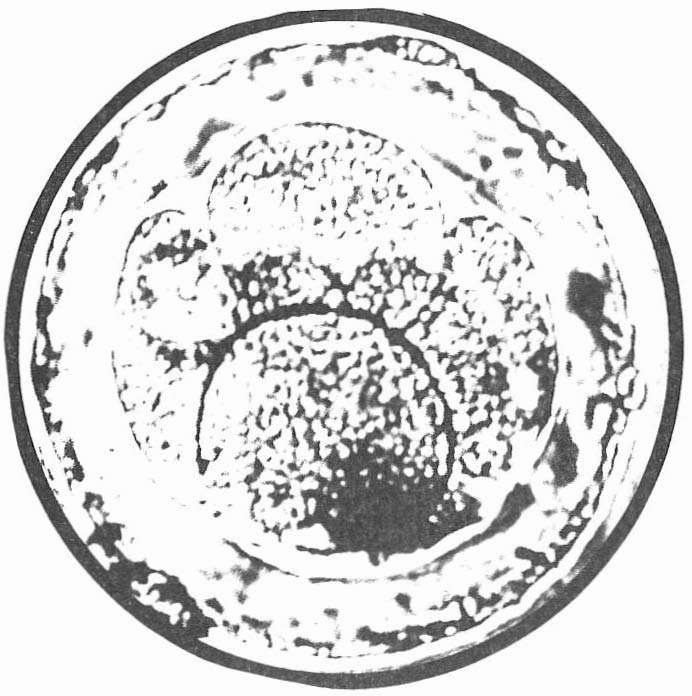

Il observe ensuite à la loupe binoculaire l’état de l’ovocyte qui vient d’être prélevé (fig. 2 et 3) ; il mesure un dixième de millimètre et, agrandi 16 fois, il ressemble à un petit nuage (fig. 4).

Fig. 4.